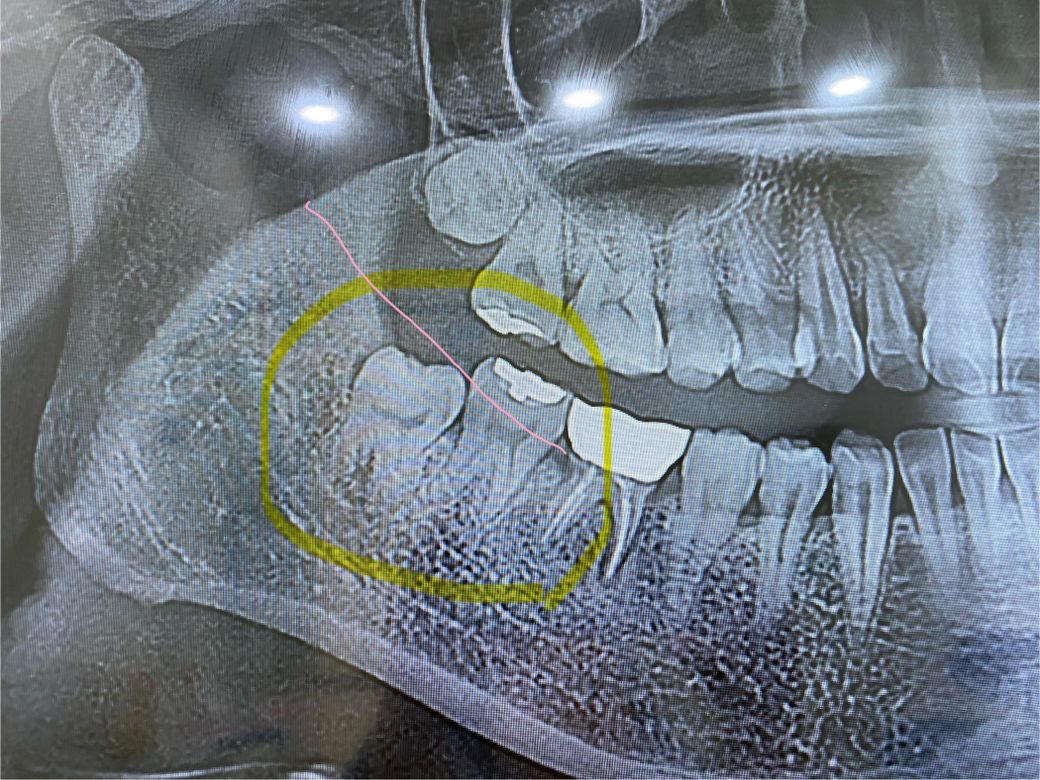

음식물이 껴서 빼려 하는데 혹시 앞어금니에 충치가 있는가요? 사랑니와 인접면 부분이요...

뭔가 거멓게 보이는 저게 뭔지 모르겠어요..

그리고 사랑니가 신경이 닿아있나여? ㅜㅜ

-엑스레이(분홍선이 잇몸살 추정?? 암튼 앞니와 경계가 저런식이에요)

엑스레이 상으로는 사랑니 앞니들의 충치는 없어 보이긴하지만 사랑니 발치를 하고 나서 다시 작은 사진을 찍어보시는게 좋을것같습니다.

매복되어 있으며 부분적으로 치조골이 덮고 있기때문에 쉬운 발치는 아닌것으로 보입니다.

사랑니 앞의 치아에는 방사선상에는 음영이 보이지만 실제로는 충치가 있지 않을 가능성이 높습니다.